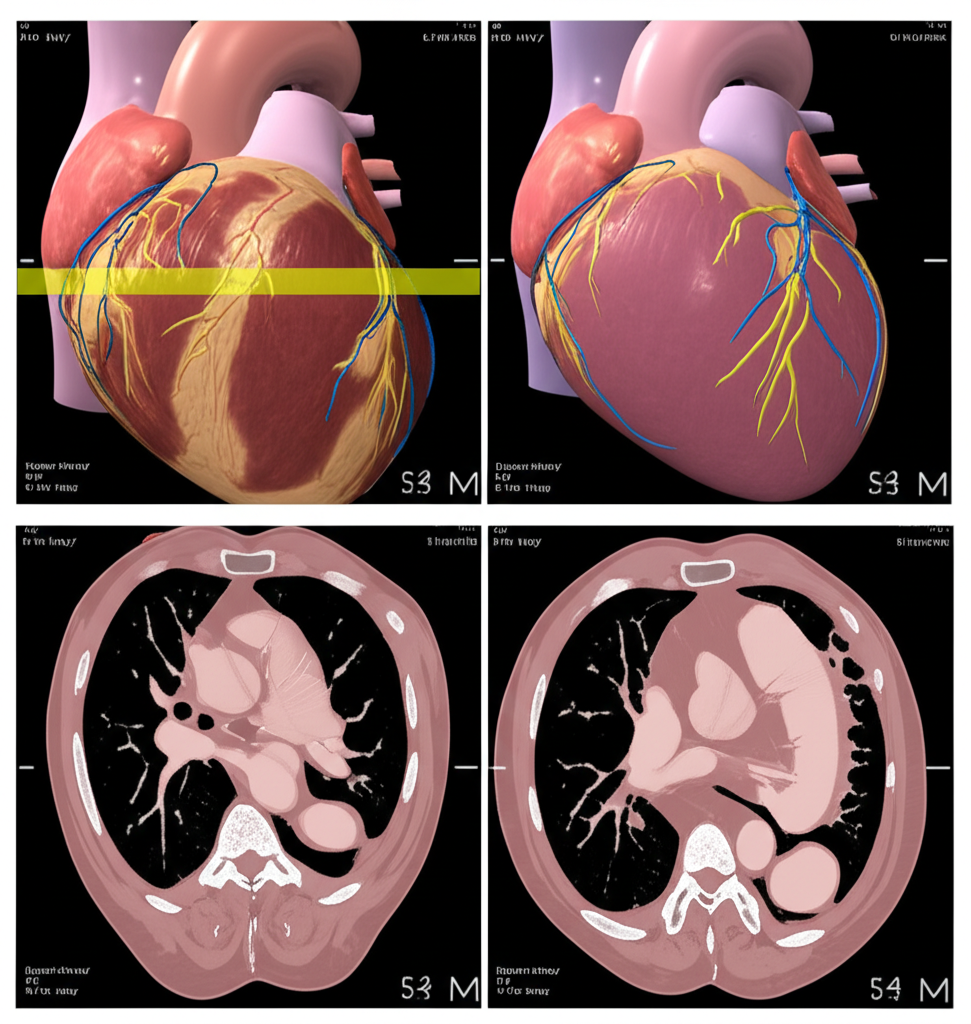

심장 CT란 무엇일까요?

심장 CT(Computed Tomography)는 컴퓨터 단층 촬영 기술을 이용하여 심장의 단면 영상을 얻는 검사입니다. 기존의 엑스레이 촬영보다 훨씬 더 자세하고 정확한 이미지를 제공하여, 심장 질환의 조기 진단과 치료 계획 수립에 큰 도움을 줍니다. 심장 CT는 특히 관상동맥 질환, 심장 판막 질환, 심근 질환 등 다양한 심장 질환을 진단하는 데 유용합니다.